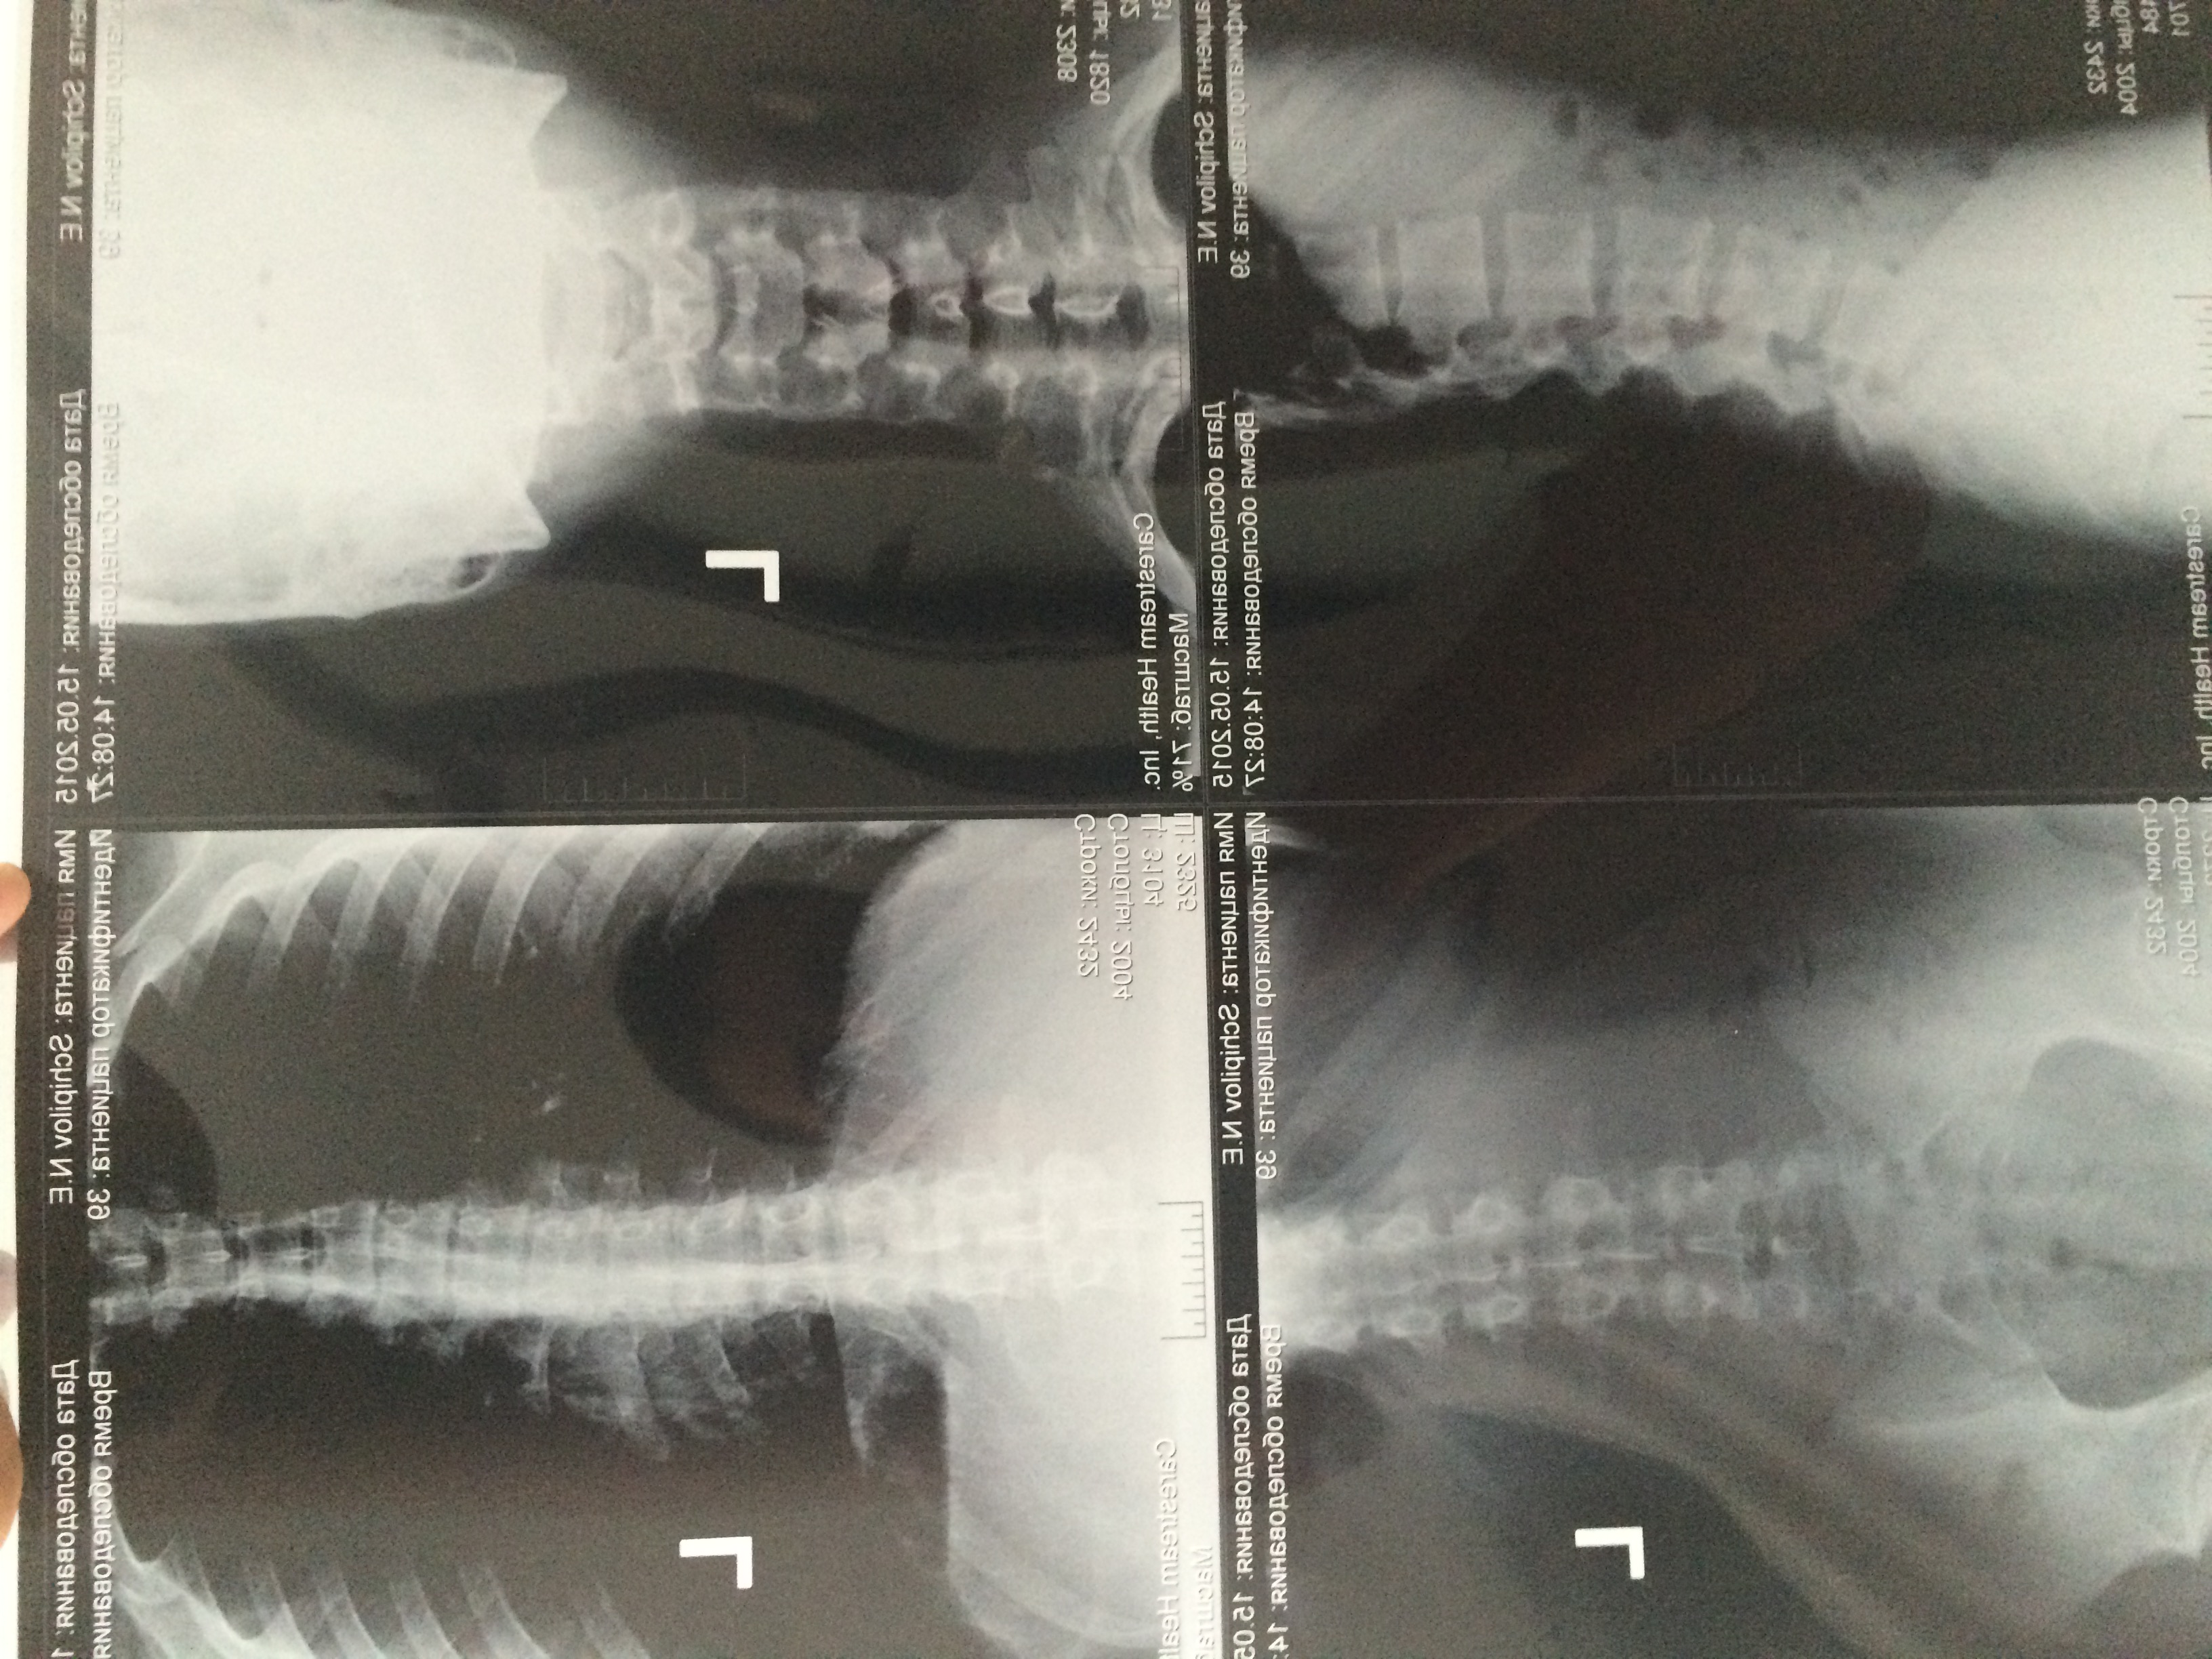

У меня проблемы со спиной.на МРТ видна протрузия 3мм в пояснице и грыжа Шморля в грудном

На цифровом рентгене-S-образная форма позвоночника и смещенные позовнки